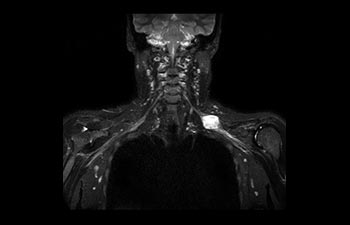

Sehen Sie selbst, was die ersten Nutzer von Ingenia Prodiva 1.5T über ihre Erfahrungen mit dem System und dessen Auswirkung auf ihre radiologische Praxis berichten.

1 Basierend auf einer internen Studie zum Vergleich des Workflows mit einem Achieva System 2 ComforTone ist ab Q4 2017 für den Prodiva 1.5T erhältlich. 3 Basierend auf einer internen Vergleichsstudie mit dem Arbeitsablauf des Achieva MRT-Systems bezüglich einer Mischung aus Gehirn-, Wirbelsäulen-, MSK- und Körperuntersuchungen 4 Normaler Betrieb ist definiert als eine typische Untersuchung mit ununterbrochener Verfügbarkeit von Strom und Magnetkühlung und ohne Wartungsmaßnahmen. 5 Abhängig von den vertraglichen Ansprüchen und der Verfügbarkeit 6 „Andere MR-Systeme“ bezieht sich hier auf Ganzkörper-MR-Systeme mit 60 cm und 1,5 T.